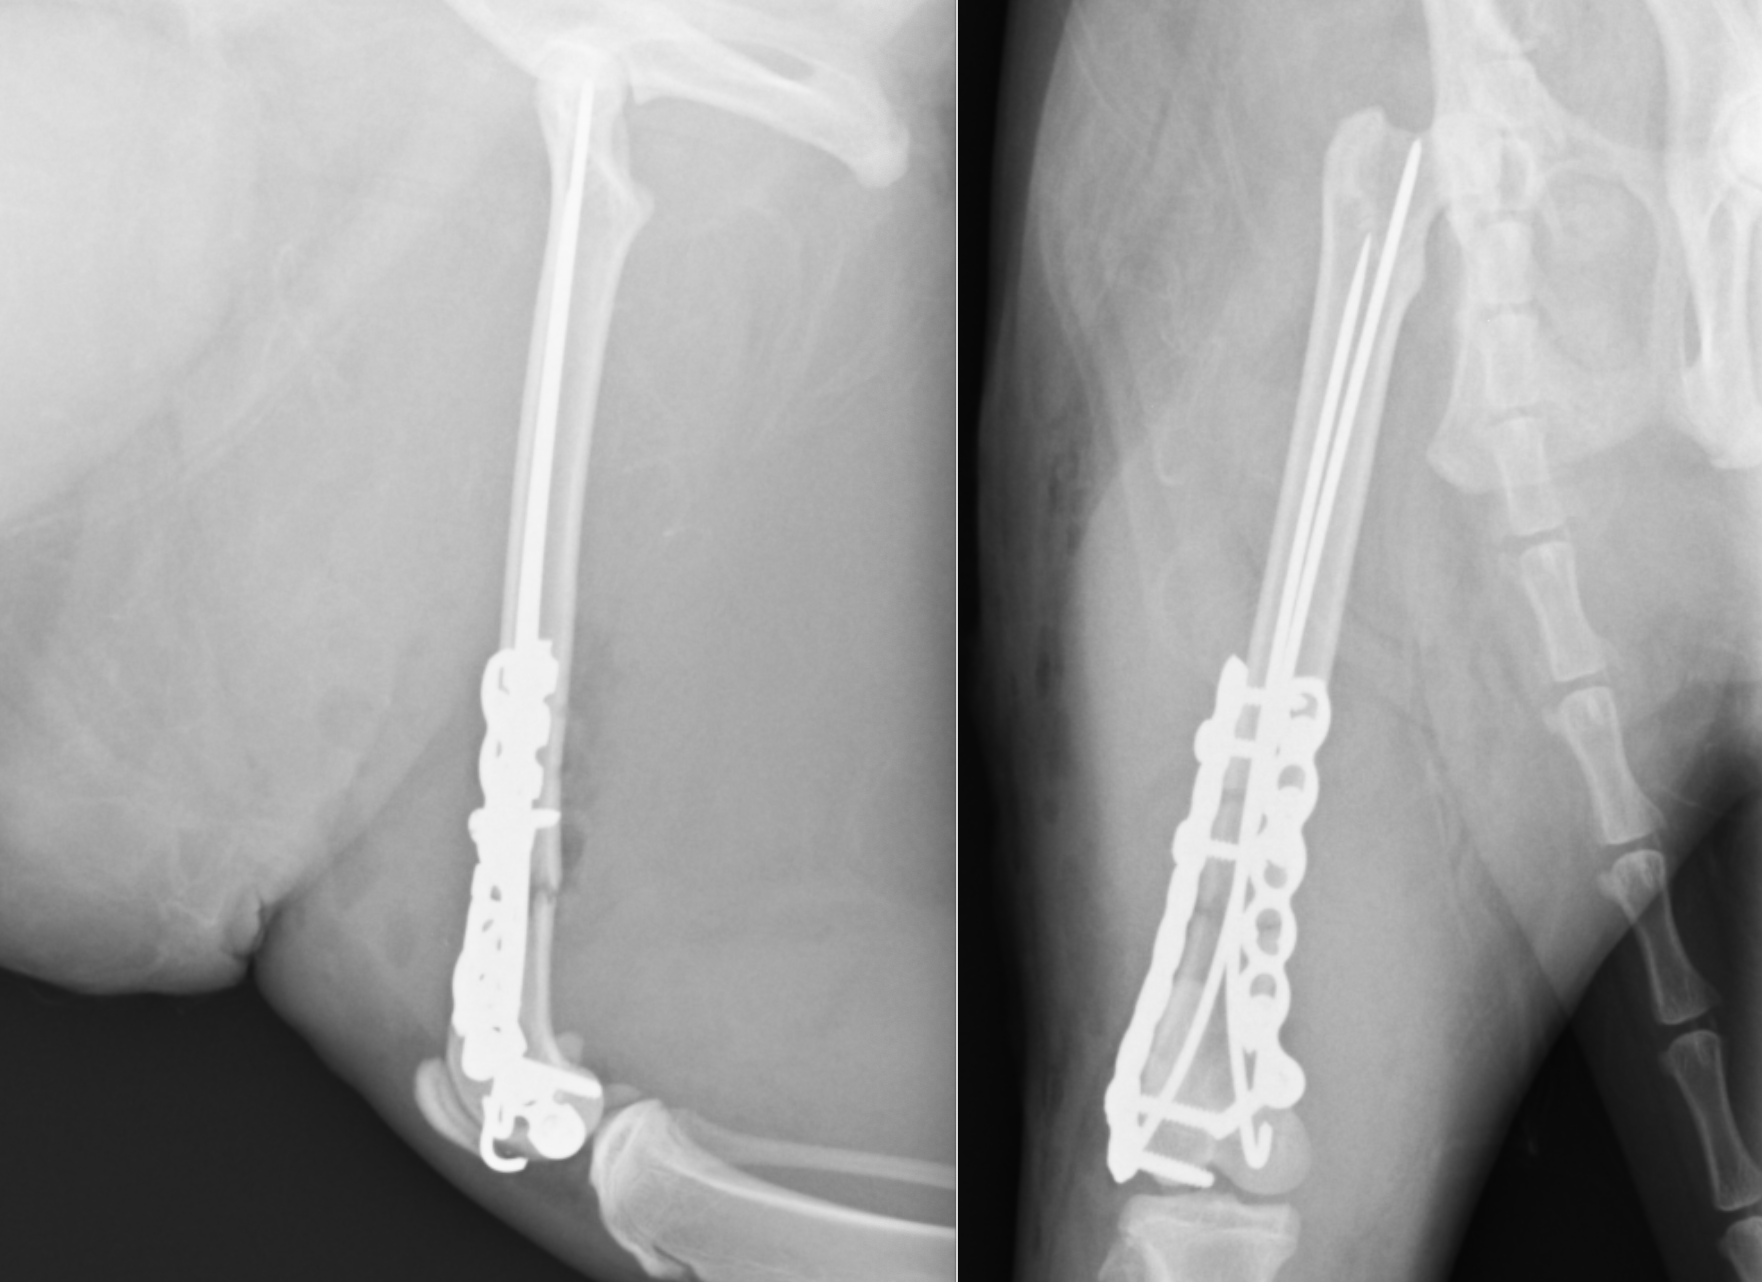

術後のレントゲンです。髄内ピンとして長いピンが2本と、外側にLCPというプレートと、ロッキングスクリュー、内側にリコンストラクションプレートと、コーテックススクリューが設置されています。

今回は術後2ヶ月ほどでプレートとピンを一部抜去しインプラントの強度を弱めました。ココまでくればもう通常通りの生活に戻ることが可能です。